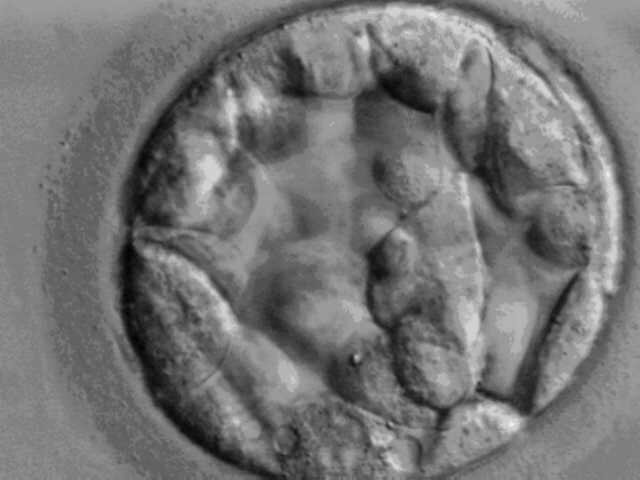

На фото вы видите бластоцисту - это самая ранняя стадия развития зародыша млекопетающих (в том числе человека). Почему она? В ней еще нет пульсации, но скоро она появится и первый удар, для зарождения новой жизни, даст что-то. Что это будет? Давайте выясним вместе.